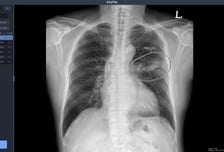

의료 인공지능(AI) 기업 뷰노가 최근 우즈베키스탄 국군중앙병원을 포함해 주요 군 병원 5곳에 인공지능 기반 X선 판독 보조 솔루션 2종을 공급했다고 23일 밝혔다. 우즈베키스탄 군 병원에 도입된 솔루션은 뷰노의 AI 기반 상지 엑스레이 판독 보조 솔루션 '뷰노메드 익스트리미티 엑스레이'와 이동형 엑스레이 장비에 AI 기반 흉부 엑스레이 판독 보조 솔루션 '뷰노메드 체스트 엑스레이'를 탑재한 패키지 제품이다. 두 제품 모두 뷰노가 과학기술정보통신부 및 정보통신산업진흥원(이하 NIPA)이 추진하는 '군 의료영상 데이터 기반 인공지능 판독 시스템 고도화 및 실증 사업(이하 군 의료 사업)'의 일환으로 개발한 제품이다. 격오지를 중심으로 현장 의료서비스가 가능하도록 설계돼 의료 인프라가 낙후한 지역에서도 진단 편차를 줄이고 의료진의 진단 효율성을 높일 수 있다. 뷰노 관계자는 "NIPA와 협력해 지난 5월 우즈베키스탄 국군 중앙병원에 제품을 설치하고, 6개월 동안의 사용성 평가를 성공적